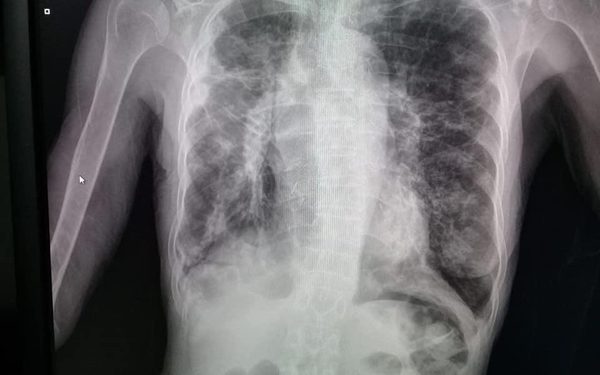

Hospital Regional de CDE realiza radiografía digital

Con esta nueva tecnología, el centro asistencial de referencia de Alto Paraná ofrece servicio de mayor precisión y rapidez para usuarios. Con la adquisición de un digitalizador de Rayos X, se suprime el uso de productos químicos para el revelado. Con esto, se estima que serán beneficiados unos 50 pacientes por día aproximadamente que requieren […] ...[Leer más]